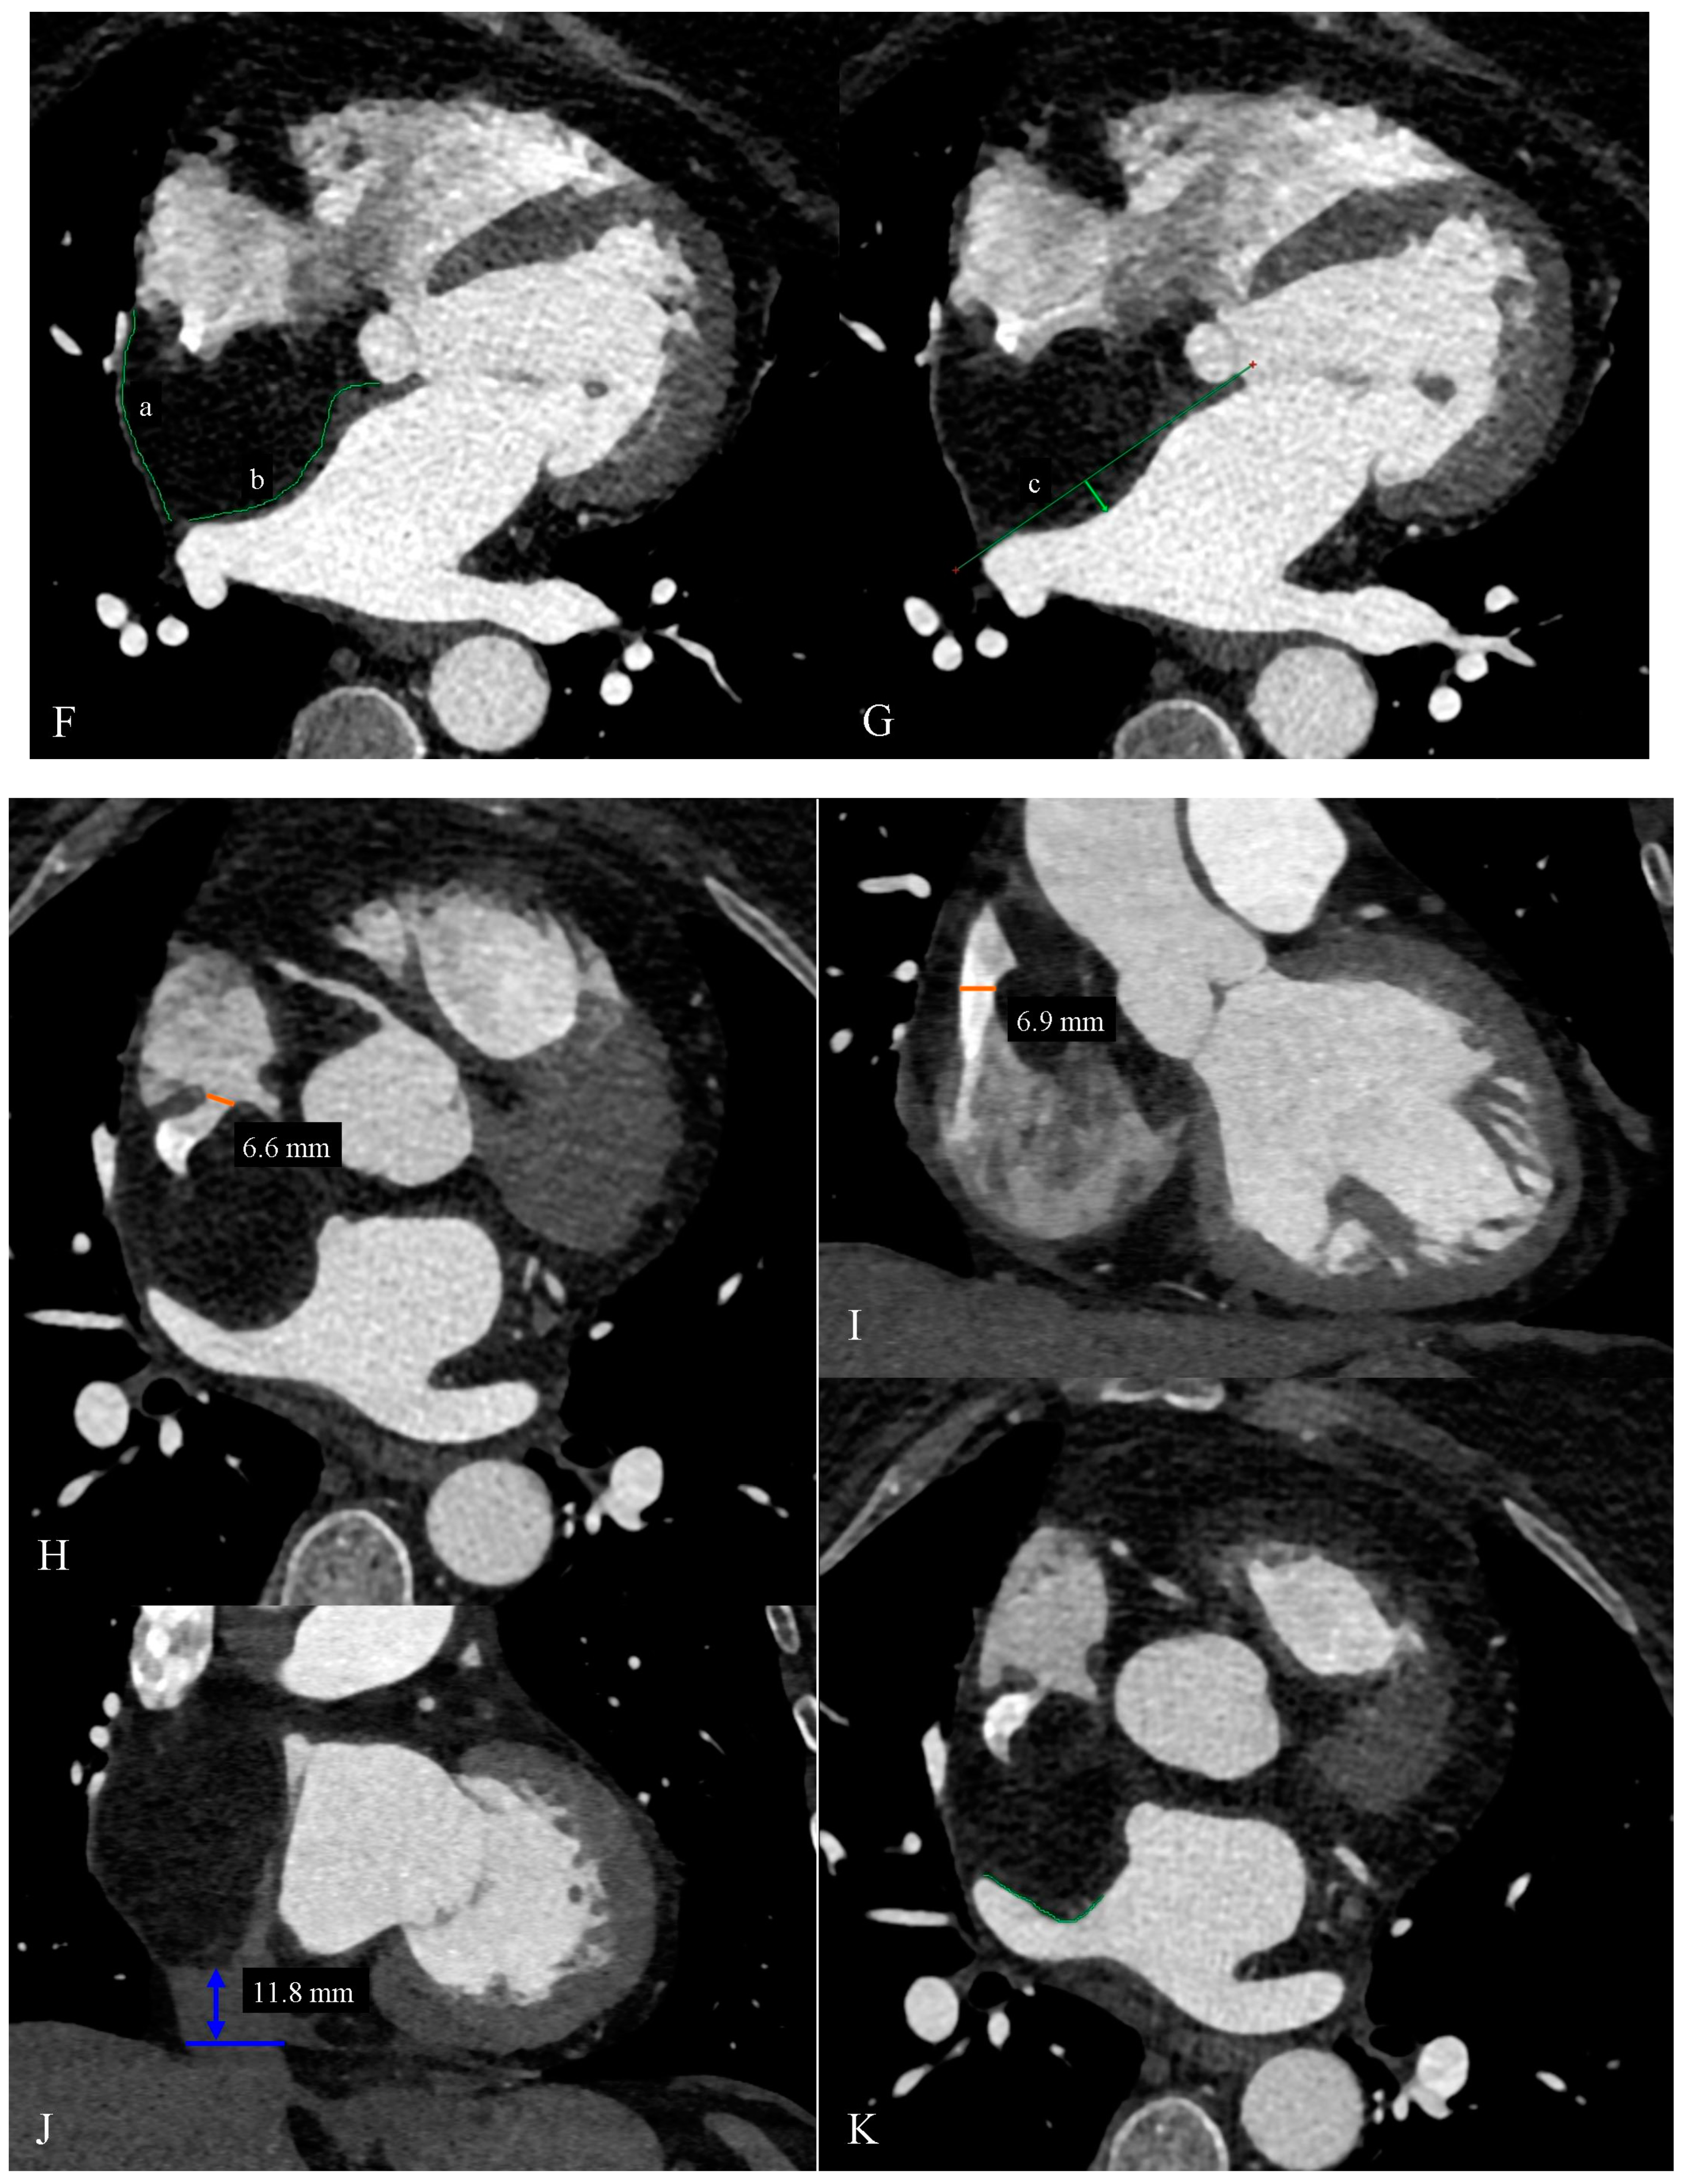

Cardiac Computed Tomography as a Method of Diagnosing the Type of Cardiac Tumor—Example of Interatrial Septal Lipoma Filling the Right Atrium

Gać, P.; Jaworski, A.; Parfianowicz, A.; Surma, A.; Jakubowska-Martyniuk, A.; Żórawik, A.; Poręba, R. Cardiac Computed Tomography as a Method of Diagnosing the Type of Cardiac Tumor—Example of Interatrial Septal Lipoma Filling the Right Atrium. Diagnostics 2024, 14, 2496. https://doi.org/10.3390/diagnostics14222496